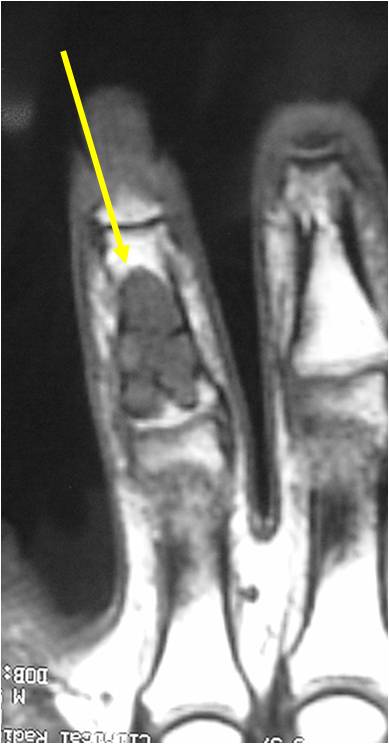

MRI:

- Lobulated margin (Lobular Growth Pattern)

- T1 Weighted Images: Intermediate Signal Intensity

- Calcifications will be low signal

- T2 Weighted Images: High Signal Intensity

- High water content shows as high signal on T2 weighted images

- Marked increased intensity long TR images

- Calcified chondroid – low intensity all sequences

- There should never be any cortical destruction nor a soft tissue component. If this exists then the tumor must be a chondrosarcoma.

- Endosteal scalloping and cortical expansion is acceptable for phalangeal tumors. In most benign long bone cartilage tumors there is minimal endosteal scalloping but there should be no cortical expansion nor thickening. There should be no cortical destruction and no soft tissue component associated with an enchondroma. Cortical destruction, periosteal thickening, cortical expansion and a soft tissue component indicates a chondrosarcoma of the long bone.

T2: High Signal No Soft Tissue Component

T1: Intermediate Signal Lobular Growth